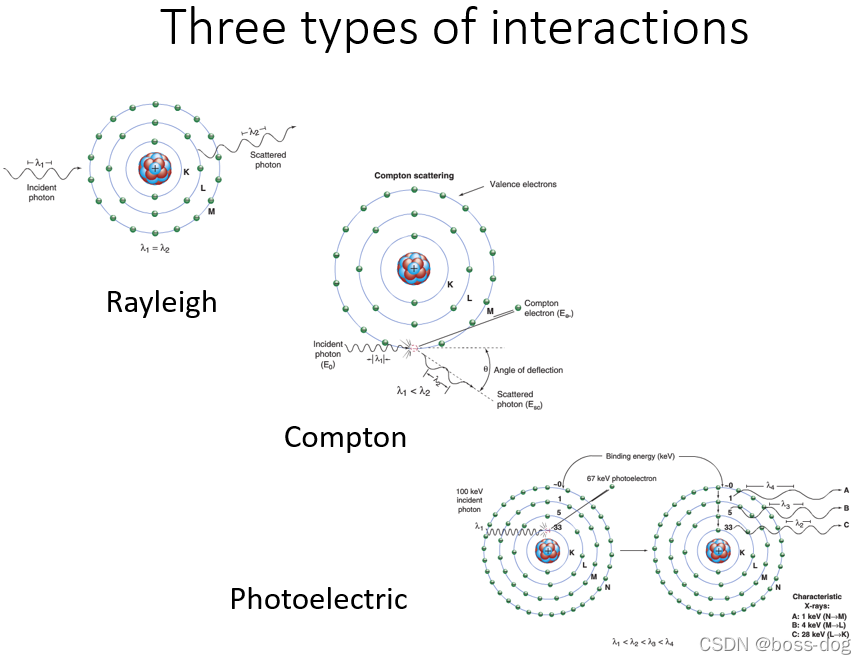

三种类型的相互作用

①康普顿散射:光子从电子上弹回,造成能量损失。就像两个台球碰撞。

②光电吸收:光子的能量完全转移到电子

③电子偶的产生:形成一个成对的正负电子

④瑞利散射(相干):光子从整个原子上弹回,没有能量损失